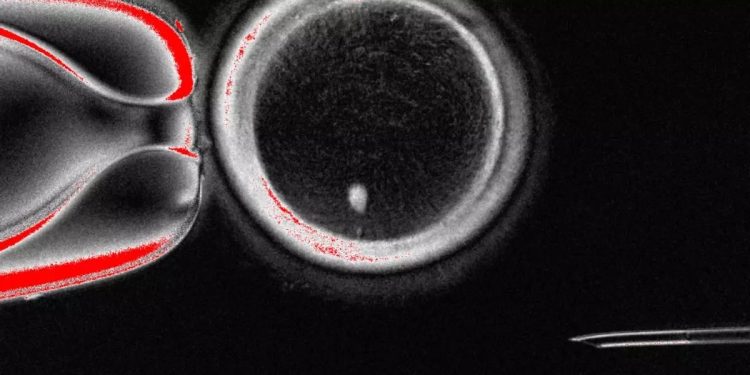

En un trabajo publicado este martes en la revista Nature Communications, el equipo de Shoukhrat Mitapilov describe cómo extrajeron el núcleo de células somáticas de la piel y lo insertaron en ovocitos de donantes sin núcleo. Esta estrategia, conocida comotransferencia nuclear de células somáticas, consiste en tomar el núcleo de una de las células somáticas del propio paciente (como las de la piel) y trasplantarlo a un óvulo de un donante con el núcleo extraído.

De cara a la reproducción, esta técnica se enfrenta a una importante dificultad: los gametos (óvulos y espermatozoides) tienen la mitad del número habitual de cromosomas (un juego de 23), mientras que las células generadas a partir de la transferencia nuclear de células somáticas contienen dos juegos de cromosomas humanos (46), lo que causaría que los cigotos posteriores tuvieran un juego adicional de cromosomas.

Los autores resolvieron este problema del juego extra de cromosomas induciendo un proceso denominado “mitomeiosis”, que imita la división celular natural y provoca el descarte de un juego de cromosomas, dejando un gameto funcional. El proceso produjo 82 ovocitos funcionales, que fueron fecundados con espermatozoides en el laboratorio. Una pequeña proporción de estos óvulos fecundados (aproximadamente el 9%) se desarrolló, al sexto día post-fecundación, hasta la etapa de blastocisto. Sin embargo, no se cultivaron blastocistos más allá de este punto, que coincide con el momento en que normalmente se transferirían al útero en un tratamiento de fecundación in vitro.

Los autores señalan varias limitaciones en su estudio, como que de los 82 ovocitos funcionales generados y fecundados, solo el 9% llegó a desarrollarse hasta el día 6, momento del fin del experimento. Además, los embriones presentaban anomalías cromosómicas. Sin embargo, consideran que esta prueba de concepto demuestra que este proceso es potencialmente factible en células humanas, lo que abre el camino a futuras investigaciones sobre la técnica.